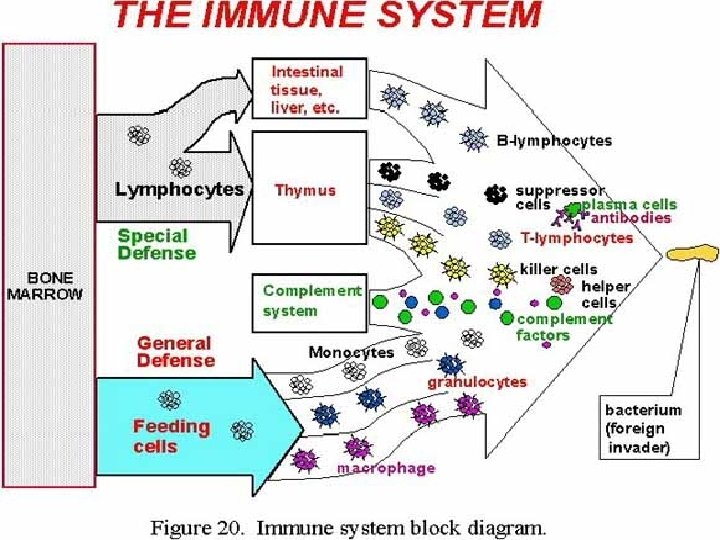

An Immune system is a collection of biological processes within an organism that protects against disease by identifying and killing pathogens and tumour cells. It detects a wide variety of agents, from viruses to parasitic worms, and needs to distinguish them from the organism's own healthy cells and tissues in order to function properly. Antigen is substance that stimulates the production of an antibody when introduced into the organism. Antigens include toxins, bacteria, viruses, and other foreign substances. Antibodies (also known as immunoglobulins, abbreviated Ig) are gamma globulin proteins that are found in blood or other bodily fluids and are used by the immune system to identify and neutralize foreign objects, such as bacteria and viruses.

The major components of the immune system are: • Immunocompetent cells • Antibodies • Complement system • Bone marrow • Thymus • Spleen • Lymph nodes • Tonsils

Immunocompetent cells: 1. T-lymphocytes {T-helper, T-suppressor, T-cytotoxic (killer cells), T-memory cells} 2. Natural killer cells(NK-cells) 3. B-lymphocytes 4. Plasma cells 5. Macrophages 6. Granulocytes of the blood(Neutrophilic, Eosinophilic, Basophilic Leucocytes) 7. Monocytes 8. Mesenhymal reticular cells 9. Epithelial reticular cells 10. Antigen Presenting Cells (APC) {Dendritic cells, Langerhans’ cells of the skin, Kupffer’s cells of the Liver, Dust cells of the Lung etc. )